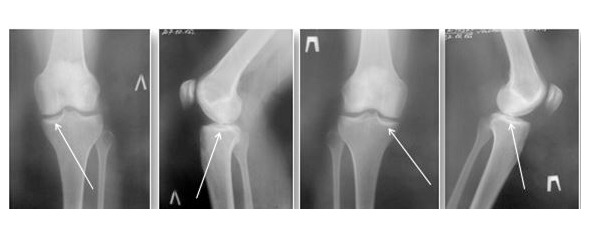

В течение болезни Кенига выделяют четыре стадии:

1 стадия – размягчение в зоне поражения участка суставного хряща;

2 стадия – появление отчетливых границ патологически измененного хряща, но сам хрящ остается неподвижным (рис. 23);

3 стадия – происходит неполное отслоение хряща с элементами его «флотирования»;

4 стадия – фрагмент хряща с участком субхондральной кости полностью отслаивается и свободно перемещается в полости сустава.

Рисунок 23. Рентгенограмма коленных суставов при болезни Кенига. Рентгенологическая картина субхондрального склероза

Клинические проявление болезни Кенига зависят от ее стадии и распространенности процесса. На ранних стадиях заболевания возникает тупая, ноющая боль, усиливающаяся при нагрузке и движениях. В дальнейшем развивается синовиит (рис. 24). Если при болезни Кенига поражается надколенник, то боль преимущественно локализуется в переднем отделе коленного сустава, под надколенником (коленной чашечкой).

Рисунок 24. Синовиит правого коленного сустава при болезни Кенига с преимущественной зоной выпота в надколенниковой сумке (верхнем завороте надколенного сустава)

При длительном течение заболевания в связи со снижением физиологической амплитуды движений в коленном суставе развивается атрофия четырехглавой мышцы бедра, что приводит к прогрессированию ортопедических проблем. Среди методов диагностики приоритетное значение имеют методы лучевой диагностики – рентген и магнитно-резонансная томография (МРТ) (рис. 25).

Рисунок 25. МР-картина структурных изменений мыщелка правой и левой бедренной кости, обусловленных инфарктом костного мозга при болезни Кенига